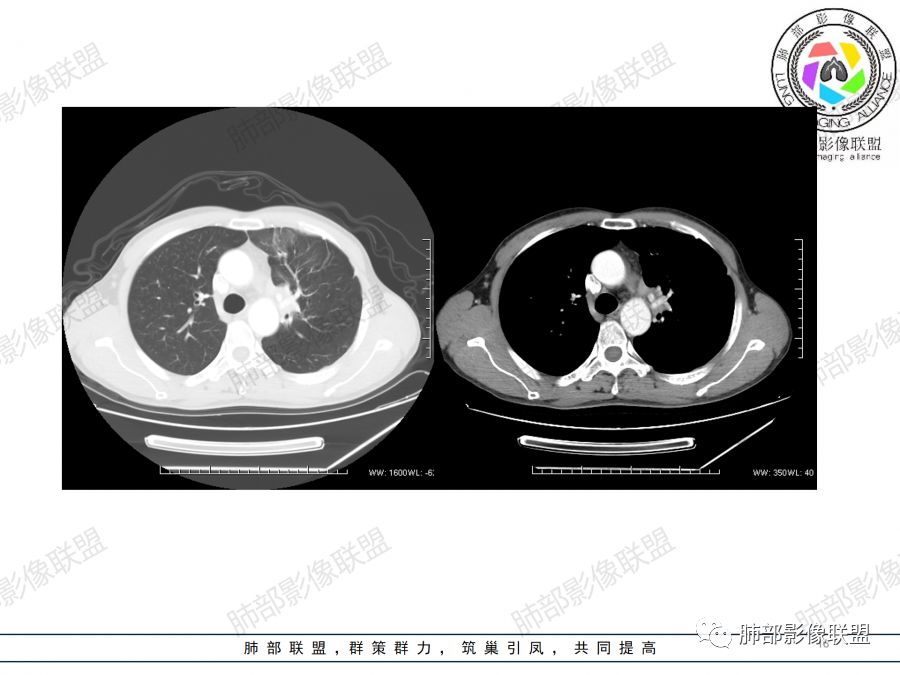

男,47岁,咳嗽咳痰一月。病灶位于左内乳动脉内缘,定位肺内,呈团片状异常密度影,整体沿支气管气管束走形分布,由肺门达胸膜下,于近肺门侧病灶形态相对较小,病灶远端相对较大,病灶整体密度偏均匀,强化偏明显,病灶内见多发支气管扩张并粘液栓形成,且扩张支气管粗细不均,直达病灶以远,病灶内血管走形正常、粗细均匀,病灶周围见边缘模糊磨玻璃及少许腺泡结节。左肺门及纵隔略大淋巴结,左侧胸膜局限性增厚。诊断:左肺上叶前段异常密度影,炎性肉芽肿性病变可能,结核不能除外,建议穿刺活检除外恶性肿瘤。

1.左肺上叶尖后段体积变化不大,病灶长轴沿支气管血管束向肺门侧生长,

2.病灶外围大,内带小,外朝内蔓延

3.病灶边缘以收缩为主,局部稍膨隆,

4.病灶整体轻中度强化,强化较均匀,局部见多个管状低密度影,边界清,考虑支气管粘液栓;病灶局部可小灶样的低密度区,未见强化,考虑坏死灶,坏死灶周围见明显强化的壁,壁清楚、光整,未见中断,倾向炎性肉芽肿的坏死;

5.病灶内血管部分走形自然,部分走形僵直、粗细不均,提示病灶有部分破坏力,但是不强;

6.病灶与纵隔胸膜呈“糊墙”样改变,倾向炎性病灶;

6.纵隔淋巴结肿大,密度均匀,强化均匀;

2.双上肺多发病灶,左肺上叶病灶沿血管支气管束分布,由外朝内,以平直收缩为主,周围有斑片渗出,胸膜糊墙,支持炎性病灶或是伴有肿瘤灶可能性。

3.病灶内多支支气管粘液栓,炎性及恶性均可,但是炎性多于恶性;强化杂乱不均,病灶内小灶坏死比规则,支持炎性肉芽肿病变。

鳞癌病灶如较大,强化常不够显著且多见相对大范围湖泊样坏死。

5.  本例的焦点主要集中在结核与周围型肺鳞癌的鉴别诊断上!

病灶与大气道的关系未能满意呈现,但如此大范围病灶紧贴胸膜却未见胸壁纵隔组织结构侵犯破坏是不大符合肺鳞癌的生物学行为的。